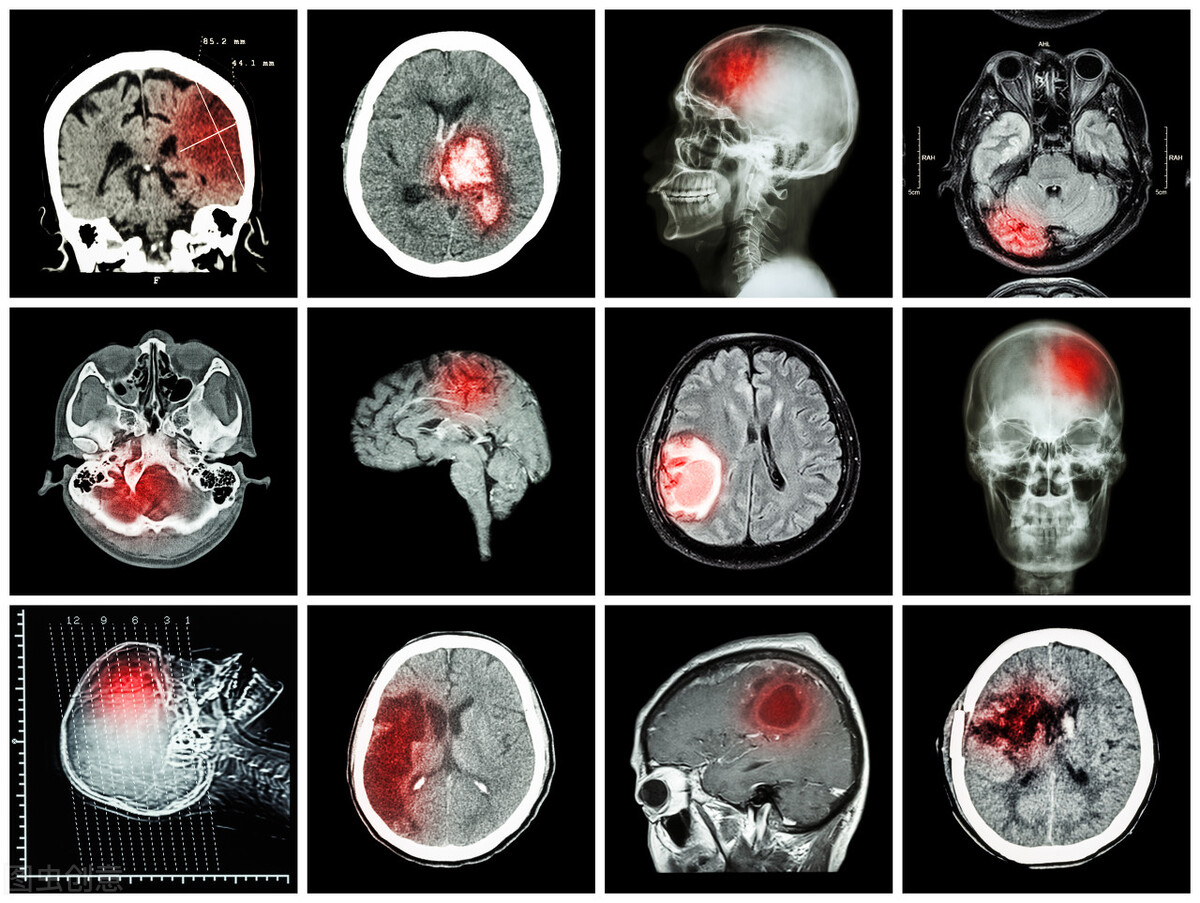

一是非脑部病变。如:血压过高或过低。二是颅内占位。关于脑部的检查,需要排除颅内有没有占位性的东西,比如脑肿瘤或脑部血肿。三是动脉瘤。一些没有破裂的动脉瘤,是需要经过血管检查去发现的。四是动脉发炎。除了动脉病变,动脉发炎也会造成血管性头痛。五是静脉堵塞。静脉堵塞也会引起血管性头痛,常见于肿瘤患者、孕妇等群体,她们的血液凝固程度比较高,容易发生静脉血栓。